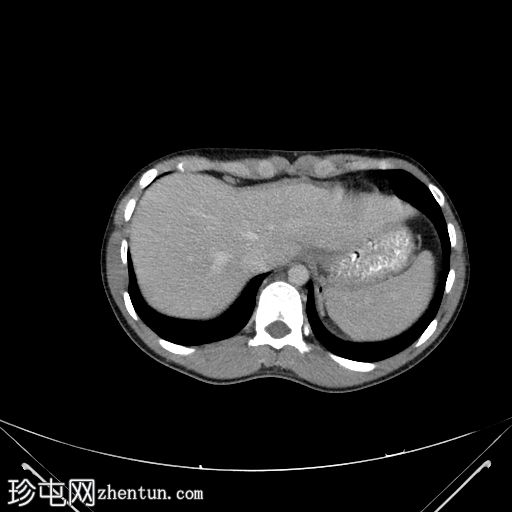

冠状位增强扫描(门静脉期)

可见盲肠和末端回肠弥漫性环周肠壁增厚,导致严重的肠腔狭窄。可见多个区域淋巴结肿大,最大者大小为2.4 x 2.2 cm,伴中央坏死。

右侧结肠旁沟可见少量游离液体和脂肪条索影,盆腔内可见少量游离液体。